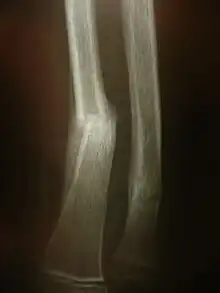

Radiologie conventionnelle

Il s'agit des examens radiologiques utilisant la technologie radio la plus « basique ». Un tube à rayon X et une plaque radiologique. Le résultat de cet examen est une radiographie (d'un membre, pulmonaire...).